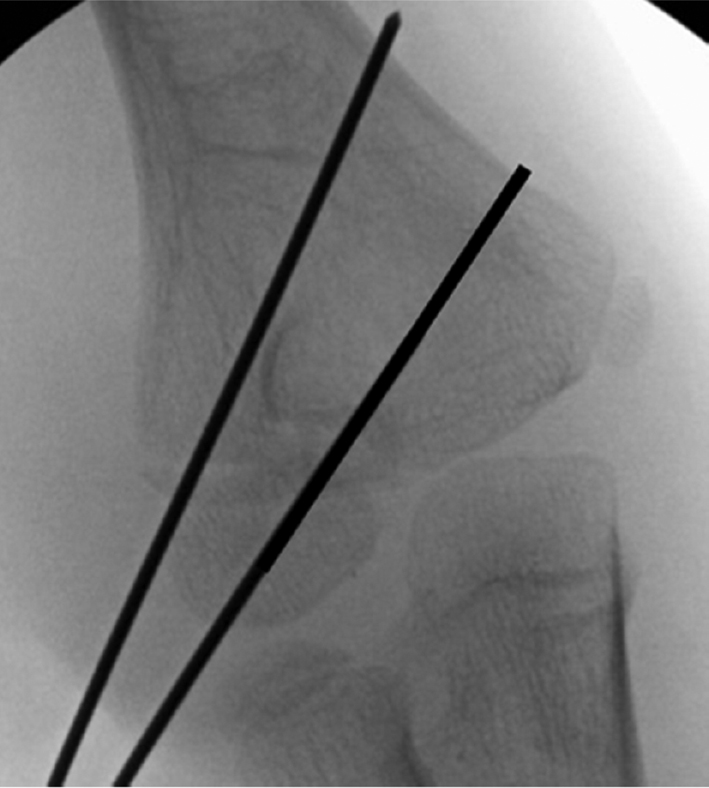

Operative Technique: The patient is prepped and draped with an extremity drape to expose up to the shoulder. An attempt at a closed reduction can be performed utilizing elbow varus and forearm pronation to disengage the fragments followed by supination and elbow valgus.4 Direct pressure with the surgeon’s thumb can improve the reduction (Figures 4–7).

Figure 4. A minimally displaced lateral fracture is partially reduced with thumb pressure.

Figure 5. A single K-wire is used to provisionally fix lateral condyle fracture.

Figure 6. Further compression can be obtained by using a cannulated depth gauge over the K-wire.

Figure 7. A second wire is divergently placed to prevent displacement, and a third wire will be placed to finalize reduction.